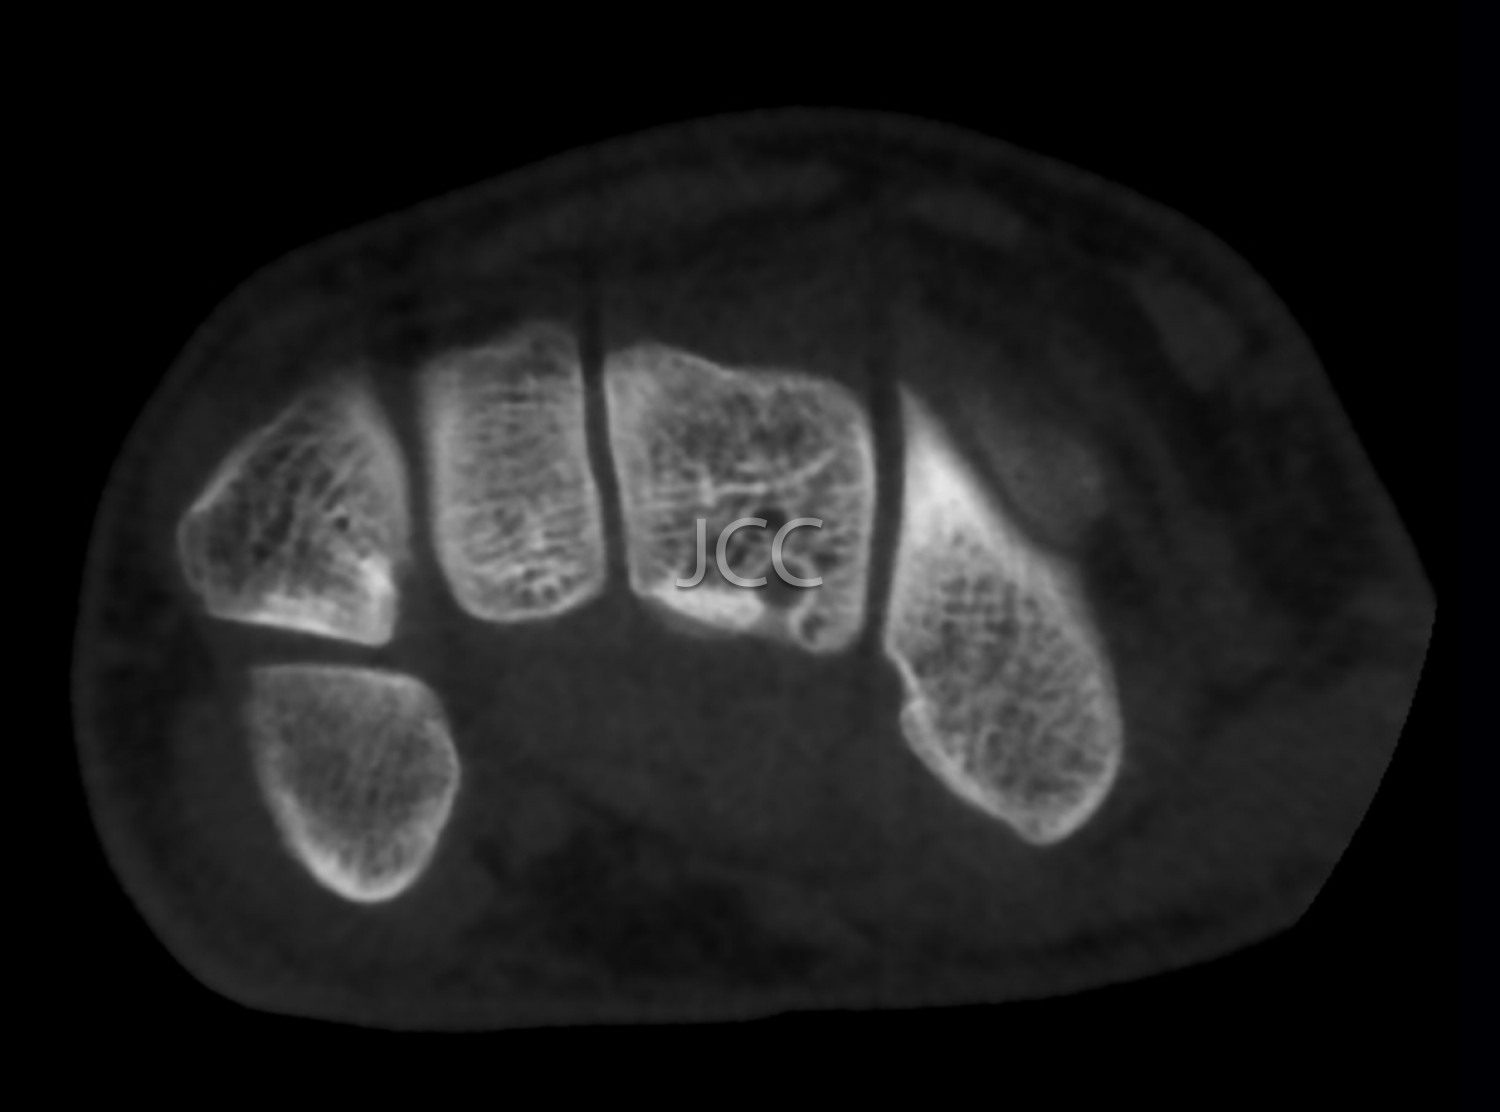

Cone Beam CT - Small Joints - Wrist / Hand / Fingers CBCT

We use a CBCT equipment which allows the study in low-dose radiation and very high spatial resolution of the bone structures of small joints, such as joints of the wrist, elbow, hands, feet, fingers, etc.

Taking into account the superior spatial resolution of the CBCT for bone evaluation compared to state of the art multi-cut CT equipment, this modality actually allows detecting small fractures or discrete small bone changes more effectively than the CT.

•Trauma to exclude small fractures

•Degenerative bone alterations